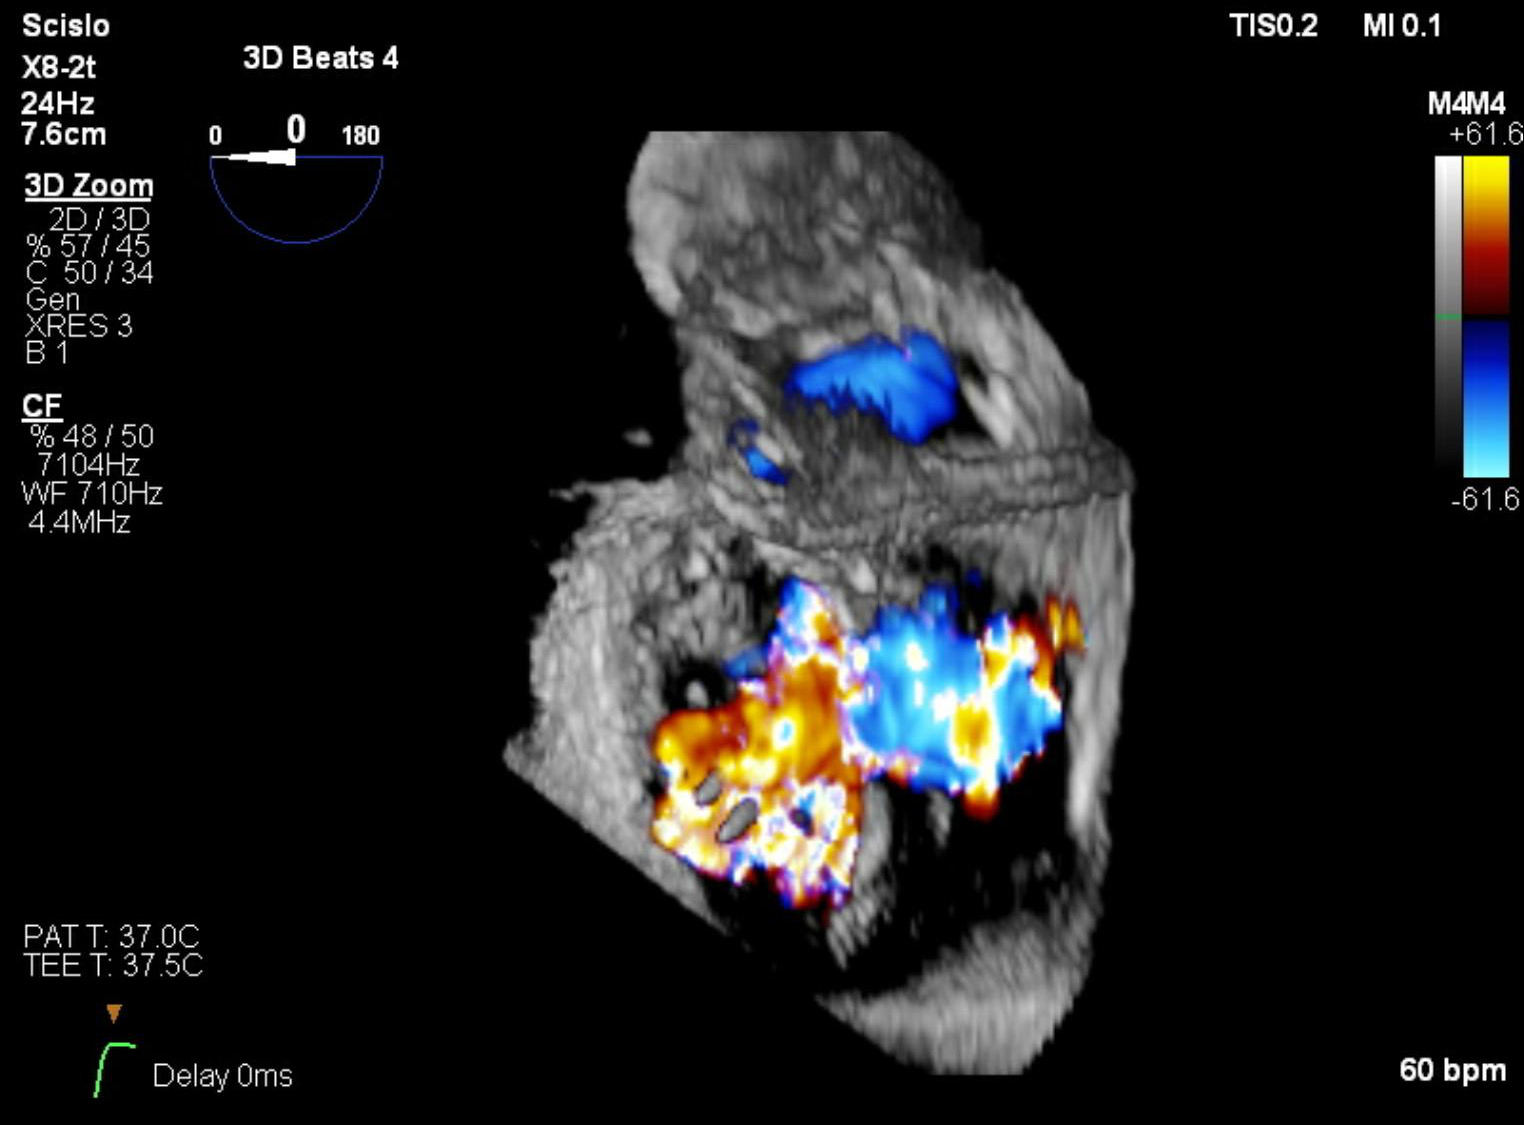

„Jak dotąd najczęściej stosowaną przez nas formą terapii był zabieg polegający na wprowadzeniu przez nakłucie żyły udowej specjalnych zapinek umożliwiających połączenie płatków, co poprawia ich przyleganie i zwiększa szczelność zastawki. Zabiegi tego typu, określane mianem przezcewnikowej naprawy metodą brzeg-do-brzegu (ang. transcatheter edge-to-edge repair – TEER), wykonuje się na bijącym sercu pod kontrolą dwuwymiarowej i trójwymiarowej echokardiografii w czasie rzeczywistym (tzw. echonawigacja). Niestety, ze względu na niekorzystną anatomię nie wszystkie zastawki można skutecznie naprawić tą metodą. W przypadku zbyt dużego poszerzenia wymiarów zastawki i oddalenia od siebie jej płatków zastosowanie klipsów może nie przynieść spodziewanego efektu; dla takich chorych rozwiązaniem mogłaby być całkowita wymiana zastawki” – tłumaczą specjaliści.

Od długiego czasu trwały intensywne badania nad opracowaniem protez zastawkowych, które można byłoby wszczepić bez konieczności przeprowadzania operacji kardiochirurgicznej, zastępując tym samym uszkodzoną zastawkę trójdzielną. Pierwsza tego typu zastawka – EVOQUE (Edwards Liefesciences, Irvine, USA) została zarejestrowana w Europie pod koniec 2023 r. Zbudowana jest ona z płatków wszytych w samorozprężalną ramkę, która jednocześnie stanowi element mocujący zastawkę w sercu. Przed wszczepieniem całość zamocowana jest na sterowalnym systemie doprowadzającym, który umożliwia przeprowadzenie zabiegu z dostępu przez żyłę udową. Procedura wykonywany jest głównie pod kontrolą echokardiografii trójwymiarowej w czasie rzeczywistym (echonawigacja).

Od 2021 r. pracujemy już z systemami zaprojektowanymi specjalnie do naprawy niedomykalności trójdzielnej, które charakteryzują się większą precyzją i skutecznością. Mimo to duża część chorych nie spełnia kryteriów anatomicznych do założenia „klipsa”: pierścień zastawki jest zbyt poszerzony, a płatki leżą zbyt daleko od siebie, by dało się je zbliżyć i skutecznie uszczelnić zastawkę. Dla tej grupy przełomem stało się wszczepienie samorozprężalnej protezy EVOQUE drogą przezżylną. Dostępna w Europie od niespełna dwóch lat zastawka jest pozycjonowana pod kontrolą echokardiografii przezprzełykowej bez otwierania klatki piersiowej. Wypełnia lukę w tej dużej grupie chorych kierowanych do zabiegów naprawczych. Za jej pomocą będziemy w stanie leczyć pacjentów, którzy są objawowi, nie mają jeszcze zaawansowanych cech niewydolności prawokomorowej, ale z drugiej strony też już mają na tyle zaawansowaną wadę, że nie można jej naprawić za pomocą dotychczasowych metod przeskórnych.

Dr hab. n. med. Piotr Scisło, kardiolog zajmujący się echokardiografią, WUM:

Chronologicznie najpóźniej terapie przezcewnikowe znalazły zastosowanie w leczeniu niedomykalności trójdzielnej. Powodem była skomplikowana anatomia i obrazowanie zastawki trójdzielnej. Przełomem dla Polski stał się rok 2018, kiedy to zespół WUM wykonał pierwszą w kraju przezcewnikową naprawę zastawki trójdzielnej metodą brzeg-do-brzegu.

Ograniczenia anatomiczne sprawiają, że nie każdy chory jest jednak dobrym kandydatem do leczenia niedomykalności metodą brzeg-do-brzegu, potrzebna jest wymiana zastawki, a nie jej naprawa. Odpowiedzią na tę lukę stała się zastawka EVOQUE – pierwsza bioproteza do przezcewnikowej implantacji w ujście trójdzielne, która została dopuszczona do użytku w Unii Europejskiej w październiku 2023 roku.